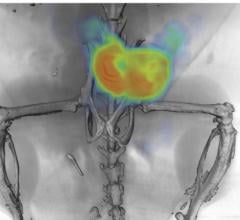

An international group of researchers report success in mice of a method of using positron emission tomography (PET) scans to track, in real time, an antibody targeting a hormone receptor pathway specifically involved in prostate cancer. This androgen receptor pathway drives development and progression of the vast majority of prostate cancers. The technique shows promise, the investigators say, as a novel way to use such an antibody to detect and monitor prostate and other hormone-sensitive cancers, as well as to guide therapy in real time.